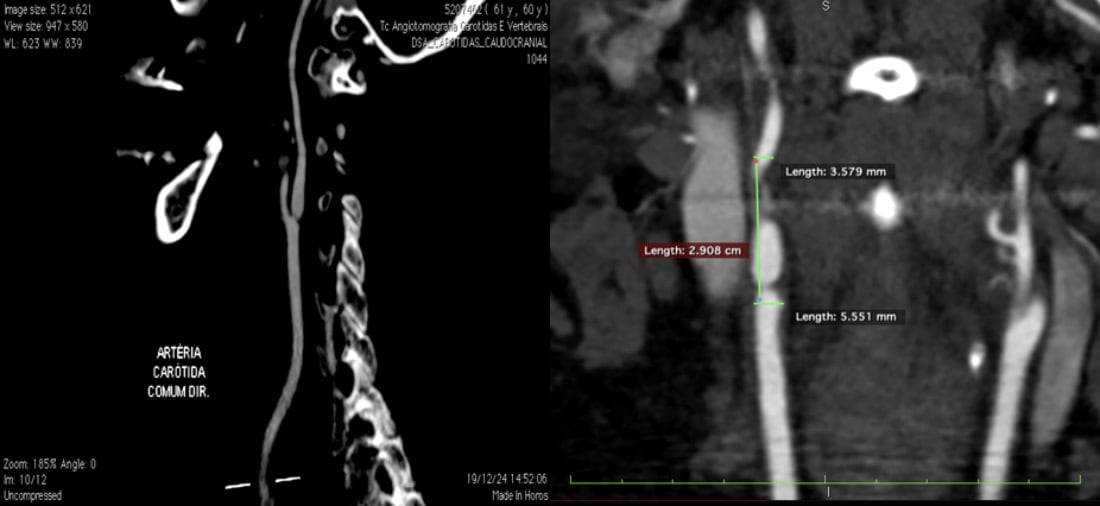

An asymptomatic 61-year-old woman, hypertensive, dyslipidemic, and obese, was diagnosed with a critical subocclusive stenosis at the ostium of the right internal carotid artery.

Imaging revealed a straight, non-tortuous vessel without atheromatous plaque, suggesting an actinic origin related to previous breast cancer radiotherapy. The patient had undergone bilateral mastectomy earlier in 2025 and was on antihypertensive, statin, and antiplatelet therapy.

- Angio CT: confirmed straight artery, no tortuosity, and without atheromatous plaques. Type I arch.

→ Hypothesis: actinic stenosis

NO atheromatous plaques